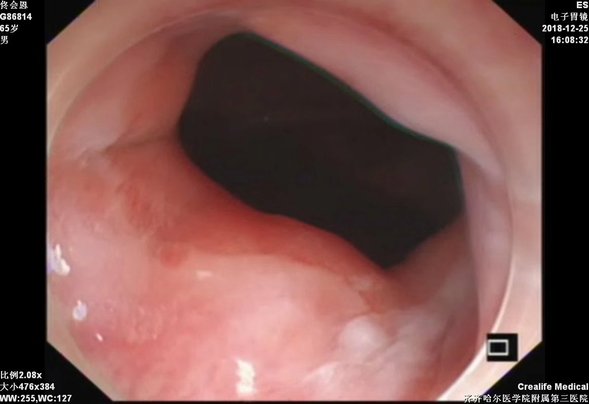

贲门黏膜下肿物